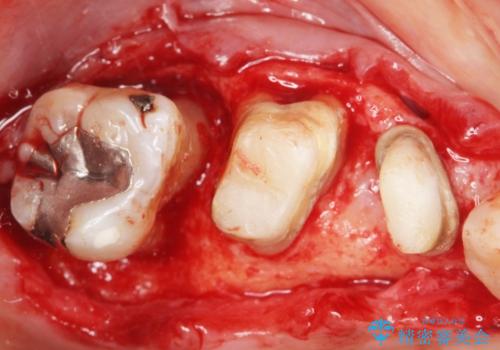

「抜歯したくない、インプラントは嫌」という患者様のご希望とご年齢を考慮し、可及的な骨外科処置や根分割術によりできるだけ今ある歯を残す治療方針をたてました。

保存不可能な左上の奥歯2本(左上67)は抜去し、ノンクラスプデンチャーをいれることにしました。

歯ぐきの腫れや出血が改善され、喜んで下さいました。

プラークコントロールを徹底して頂き、できるだけ歯が長持ちするよう今後も定期検診でフォローさせて頂きます。

- 外科手術のため、術後に痛みや腫れ、違和感を伴います